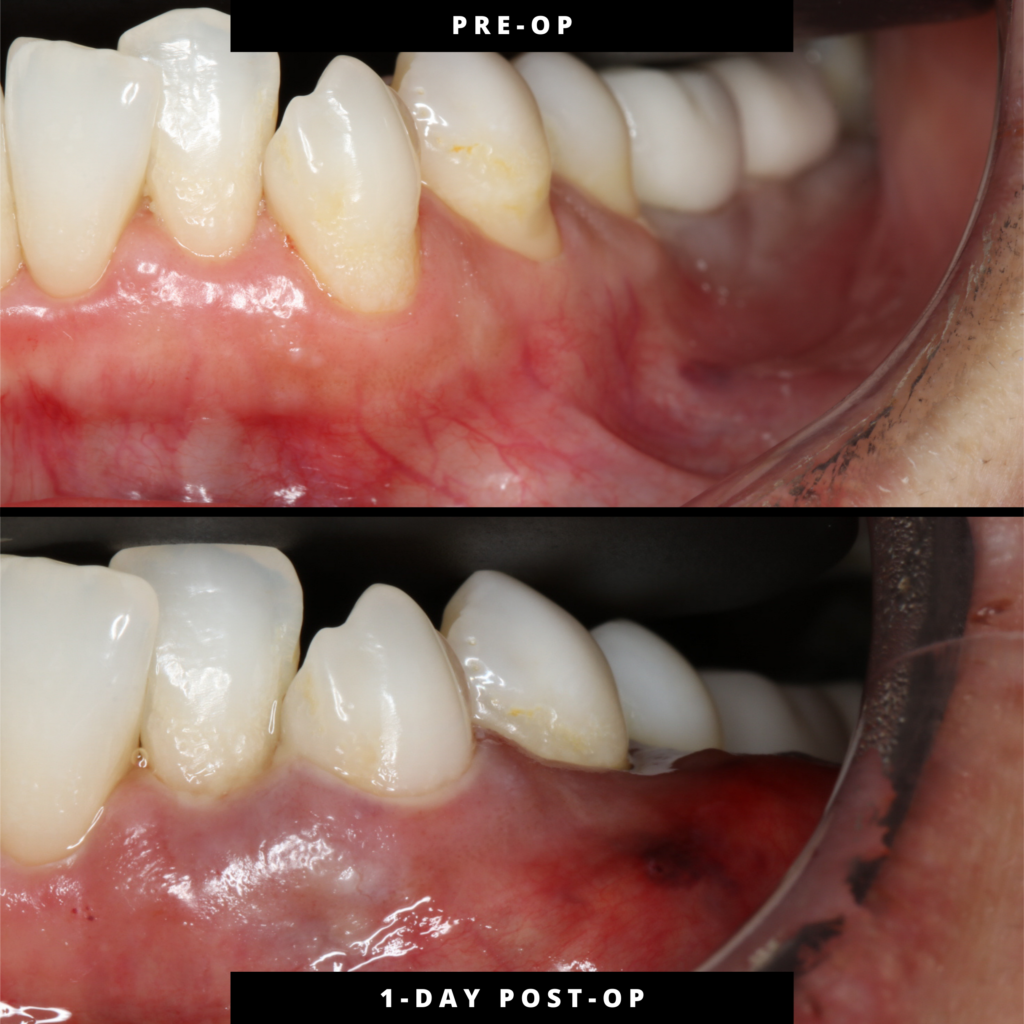

This entry documents a post-operative day 1 clinical observation following treatment of gingival recession at teeth #20–21 using the Pinhole® Surgical Technique.

At this acute interval, the treated site demonstrates expected early-phase edema and localized erythema with maintained soft-tissue positioning. Final gingival margin position has not yet declared, as continued biologic remodeling is expected during maturation.